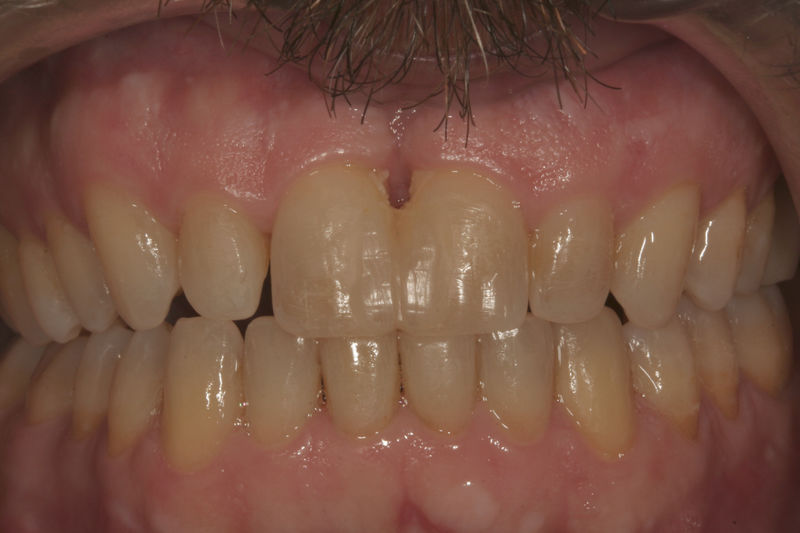

Implantes, ortodoncia y coronas.

Ortodoncia y coronas.